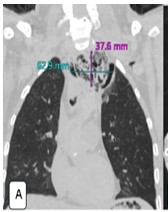

Boerhaave syndrome (BS) is a rare, life-threatening condition characterized by spontaneous esophageal rupture, commonly triggered by forceful vomiting. Due to its nonspecific presentation, BS is often misdiagnosed, leading to delayed intervention and high mortality. We report a case of BS presenting with hematemesis, respiratory distress, and collapse, emphasizing the forensic implications and the role of postmortem computed tomography (PMCT) in virtual autopsy. A 46-year-old male with a history of alcohol consumption experienced sudden-onset hematemesis and respiratory distress, followed by cardiopulmonary arrest. Despite resuscitation efforts, the patient was pronounced dead. Autopsy findings revealed a full-thickness esophageal rupture with mediastinal contamination and pleural effusions, confirming BS as the cause of death. PMCT successfully detected pneumomediastinum, free intrathoracic air, and mediastinal fluid, demonstrating its utility in forensic investigations. The case highlights key differential diagnoses of sudden death, including acute myocardial infarction, pulmonary embolism, and aortic dissection. This case aligns with existing literature where hematemesis, though less commonly reported, was a significant symptom preceding cardiovascular collapse. Delayed diagnosis of BS remains a critical factor contributing to poor outcomes and increased mortality rates. The integration of PMCT with conventional autopsy enhances the diagnostic accuracy of esophageal perforation-related deaths, particularly in forensic settings. Comparative analysis with previously reported cases underscores the need for heightened clinical suspicion and early imaging to prevent fatal outcomes. Boerhaave syndrome remains a diagnostic and therapeutic challenge, often leading to sudden and unexpected death. This case reinforces the medicolegal importance of virtual autopsy in identifying esophageal rupture, particularly in unwitnessed or unexplained deaths.